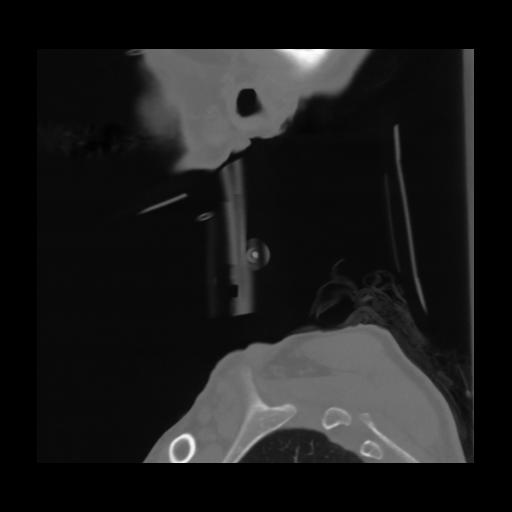

14 P.BLANDAS,,Sagittal,2.000,P.BLANDAS,Sagittal,